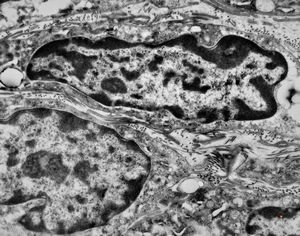

F,41y. | synovial metaplasia - capsule of implantate

F,41y. | synovial metaplasia - capsule of implantate

F,41y. | synovial metaplasia - capsule of implantate

F,41y. | synovial metaplasia - capsule of implantate

F,41y. | synovial metaplasia - capsule of implantate

F,41y. | synovial metaplasia - capsule of implantate

F,41y. | synovial metaplasia - capsule of implantate

F,41y. | synovial metaplasia - capsule of implantate

F,41y. | synovial metaplasia - capsule of implantate